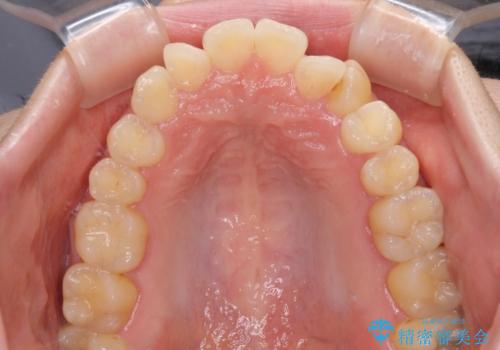

- 八重歯を気にして来院された患者様です。

診査を行ったところ、下顎前歯が1本欠損しており、下顎歯列が上顎よりも小さくなっていることで、上顎にデコボコが生じていました。

口元を見ると抜歯をして突出感を改善するような状態ではなかったため、上顎歯列のデコボコを整えて、歯列全体を後方に移動させることでバランスを取ることとしました。

思っていた以上に上顎歯列を後方に移動させることができ、すっきりとした口元に仕上げることができました。